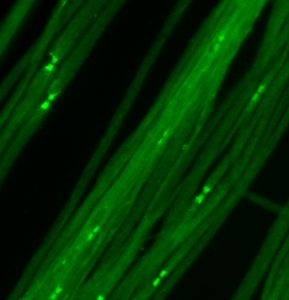

„Wir konnten feststellen, dass bei einem Teil der Patienten Antikörper gegen das Protein Caspr vorliegen“, schildert Kathrin Doppler das zentrale Ergebnis dieser Studie. Caspr ist am Aufbau der sogenannten Ranvierschen Schnürringe beteiligt – einer Struktur an der Nervenfaser, die besonders wichtig für die Weiterleitung von Nervenimpulsen ist. Die Wissenschaftlerinnen konnten zeigen, dass bei Patienten mit Antikörpern gegen Caspr der Aufbau der Ranvierschen Schnürringe zerstört wird und die Nervenleitung stark beeinträchtigt ist.

Auch wenn Antikörper gegen Caspr nur bei einem kleinen Teil der Patienten nachweisbar sind, so sind Antikörper-assoziierte Immun-Neuropathien insgesamt vermutlich häufiger, als bislang angenommen. Caspr ist nämlich schon das dritte Protein in diesem Bereich des Ranvierschen Schnürrings, gegen das nun Autoantikörper nachgewiesen wurden. Neben den Würzburger Neurologinnen haben in den vergangenen Jahren auch Wissenschaftler aus Spanien und Japan Autoantikörper gegen zwei andere Schnürringproteine, Contactin-1 und Neurofascin-155, bei Patienten mit Immun-Neuropathien nachweisen können.